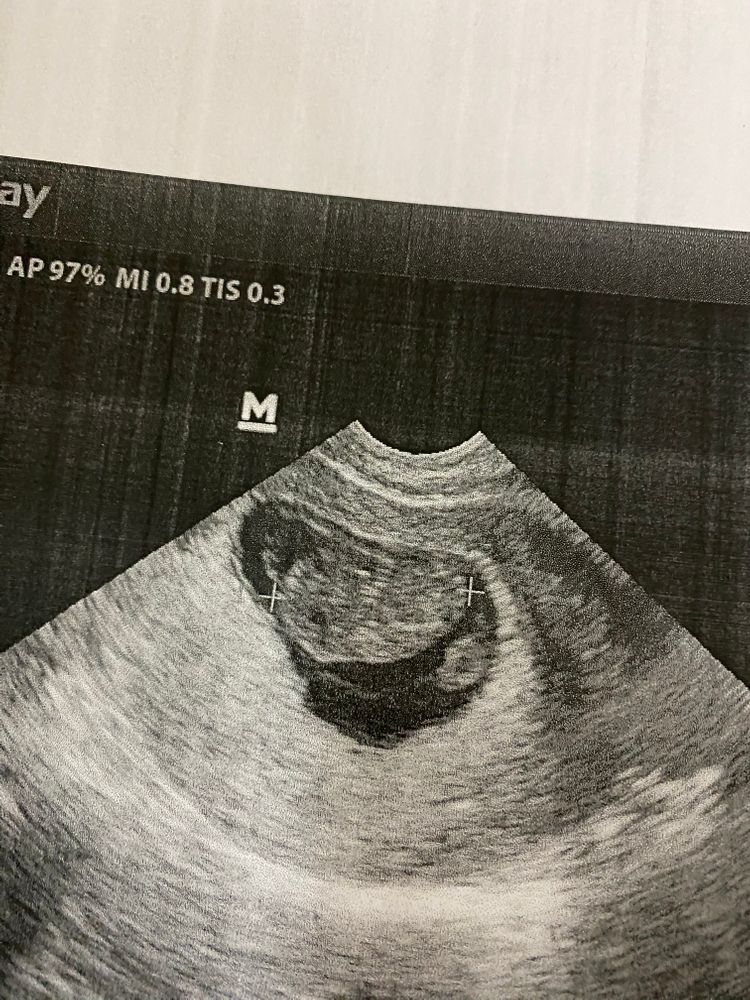

Ну что, мои дорогие мамочки! Вот наконец-то сходили вчера на долгожданный скрининг.Очень волновалась, так как неделю назад гинеколог напугала меня замершей беременностью, по маленьким размерам матки. Но узи показало, что все у нас прекрасно, Малыш уже подрос, во всю шевелиться. Не могли его толком поймать, чтобы сделать красивый снимок)

Показал наш мальчик все свои прелести. Сказали 100%мальчик. Девочки, когда вам сказали пол, и подтвердилось ли в итоге ?

прикрепляю вам наше маленькая счастье с 5 недели, до сегодняшнего дня ❤️❤️